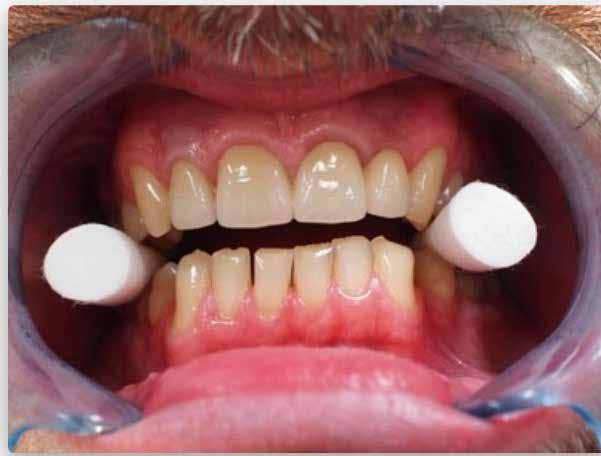

A 38 éves hölgy páciens a jobb alsó második kisőrlőfog területéről (45) eredő fájdalom miatt kereste fel rendelőnket. A panaszai rágás közben fokozódtak. A páciens általános anamnézisében nem szerepelt semmi kiemelendő. Elmondása szerint a bal alsó kisőrlőfogát korábban gyökérkezelték, valamint 7 évvel ezelőtt fogszabályzó kezelésben részesült. A klinikai vizsgálat során a kérdéses fognál kopogtatási érzékenységet regisztráltunk, illetve a fog disztoapproximális felszínének megfelelően több mint 3 mm-es tasakmélységet mértünk.

A radiológiai felvételek elemzése során a fog gyökércsúcsának megfelelően radiolucens elváltozást észleltünk, valamint a fognyak területének megfelelően szintén egy radiolucens területet figyelhettünk meg (1–2. ábra). Az elváltozások kiterjedésének és mélységének pontosabb meghatározása érdekében CBCT-felvétel készült (3. ábra). A felvétel alapján Heithersay-féle III. osztályú külső fognyaki gyökérfelszívódást diagnosztizáltunk (Heithersay Class III external cervical invasive root resorption; ECIR). Ezzel egyidejűleg pedig szimptomatikus periapikális periodontitis is fennállt. Ezt követően a pácienst a vizsgálati eredményekről, a kezelési alternatívákról és a várható prognózisról is tájékoztattuk.